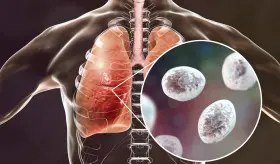

La gripe no solo daña los pulmones, también altera su equilibrio bacte...